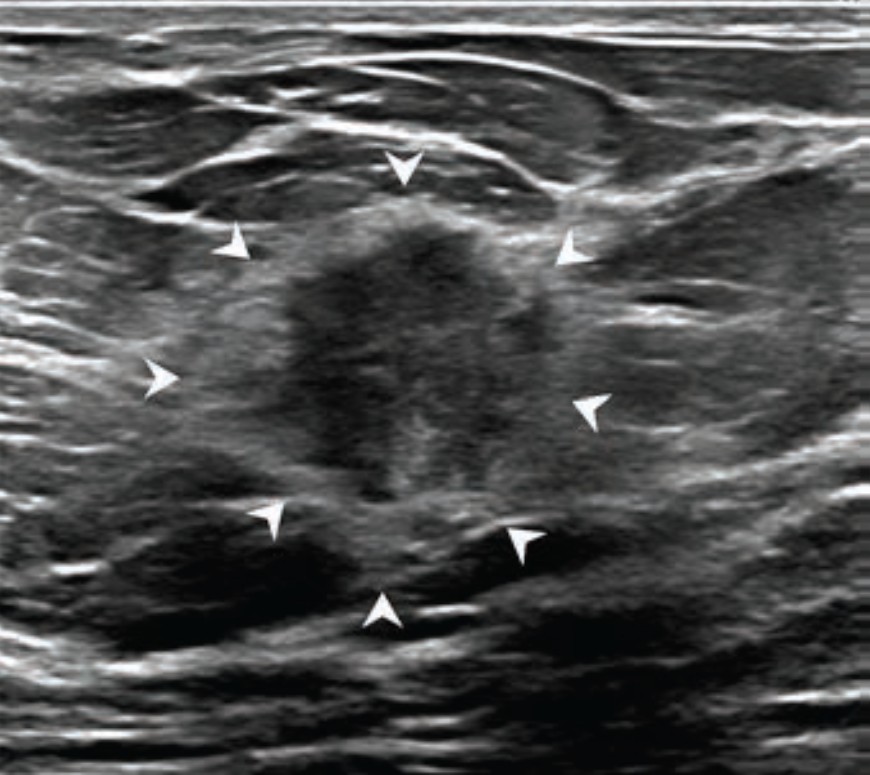

Images in a 53-year-old woman with a nonmass lesion detected at preoperative evaluation of newly diagnosed right breast cancer. (A) T1-weighted early contrast-enhanced axial preoperative MRI scan shows focal nonmass enhancement in the left upper-outer breast (arrow). (B) Transverse and (C) longitudinal ultrasound images show a nonmass lesion (arrows, crosses) in the left upper-outer breast with several adjacent small cysts (arrowheads). (D) A T2-weighted fat-suppressed axial MRI scan also shows a small cyst (arrowhead) in the corresponding area. (E) Left mediolateral oblique mammogram shows heterogeneously dense breast tissue without findings suspicious for cancer. The lesion was confirmed to be ductal carcinoma in situ with ultrasound-guided core biopsy and subsequent surgery.RSNA